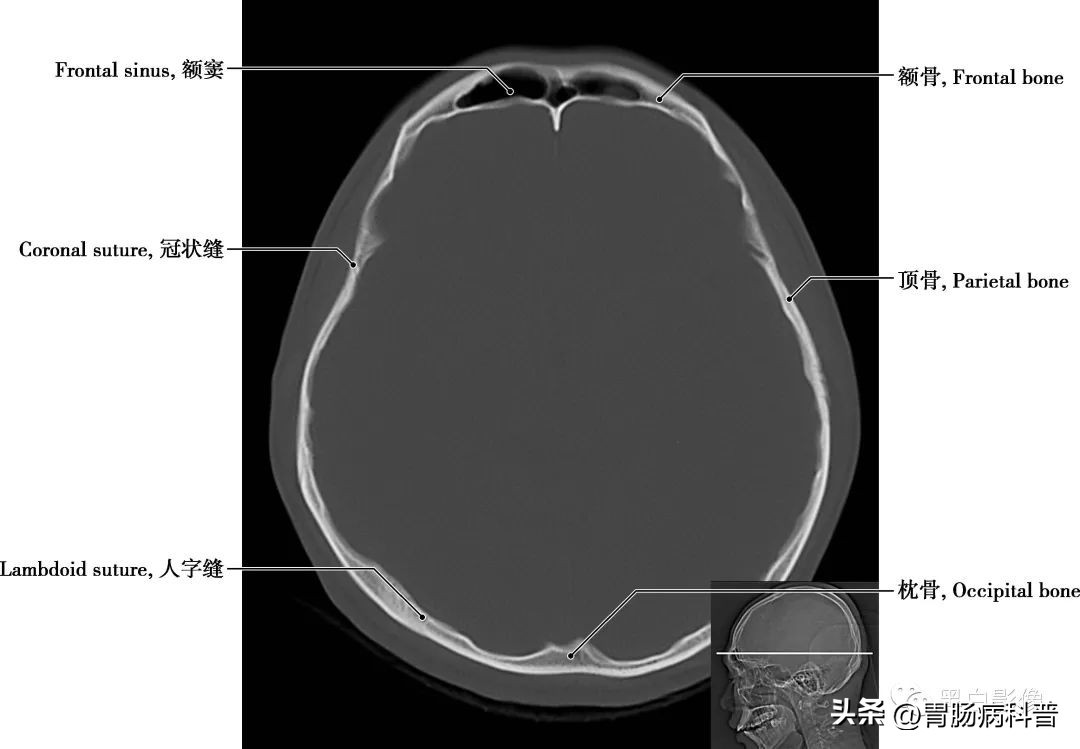

图1-2-1 经顶骨轴位切面

顶骨 位于颅盖的中部,左右各一,呈四边形,为外凸内凹典型的扁骨